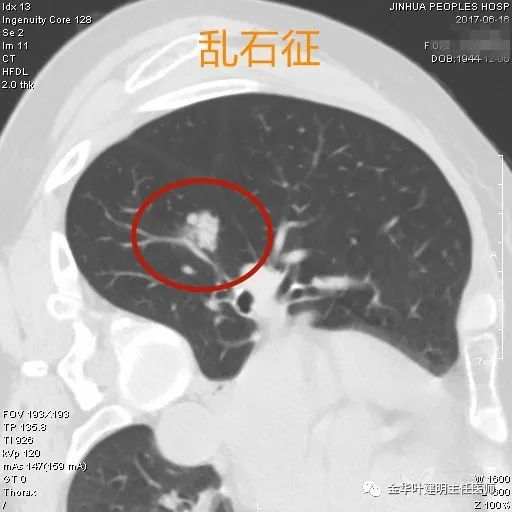

乱石征

乱石征:这个名称也是我自己想想的,病灶偏实性,就像多个小石头堆在一起,乱石堆砌的感觉。这时如果病灶的轮廓又很清晰,周围肺组织也无渗出的改变,那么极可能是恶性的。些征用在密度低的混合磨玻璃结节上也适用,其实性部分密度杂乱时也类似道理。